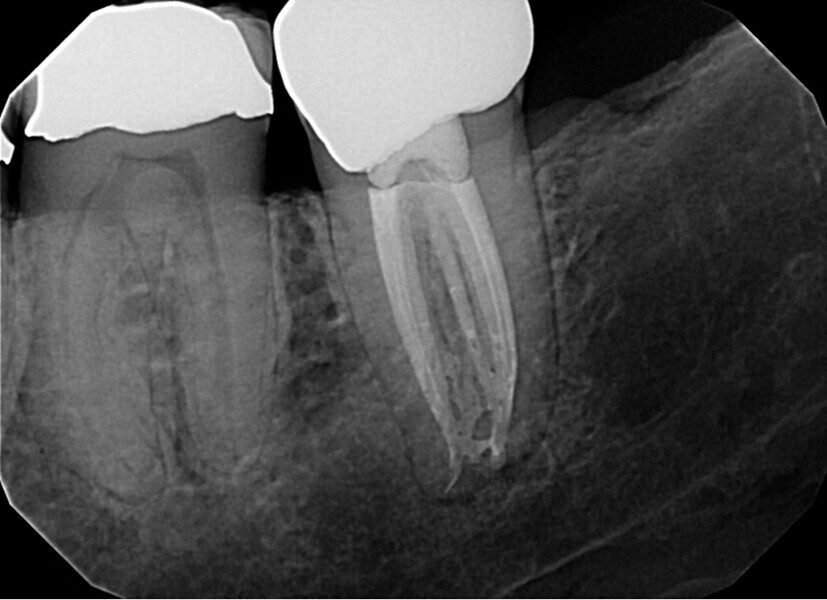

Fig. 14a: Case treated with Bassi Logic controlled memory nickel titanium files. Note the visualization of the third root on this lower molar and conservative canal preparation shape. (Courtesy of Dr. Alex Chan)